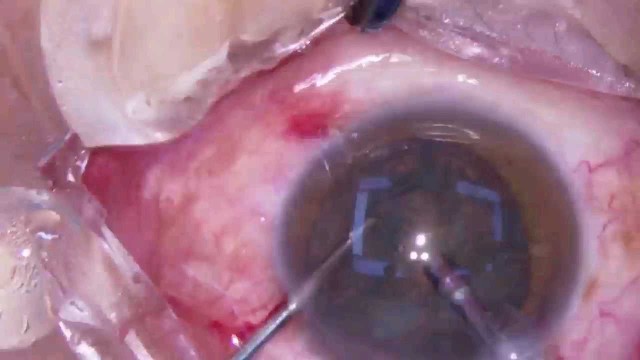

大瓜:湖南省人民医院副院长出轨眼科主任?

号外号外,湖南省人民医院副院长祖雄兵和眼科主任医师曾琦被指存在不正当关系,并有不雅视频传出。对此,医院工作人员回应:组织正在调查,请给医院宣传部门联系。当地卫生健康委员会对此回应:暂未接到相关的信访反映。祖雄兵为湖南省人民医院副院长,泌尿外科学科带头人。曾琦,博士,主任医师,硕士研究生导师。现任湖南省人民医院眼科副主任、眼科一病区主任,湖南省卫生健康高层次青年骨干人才,湖南省预防医学会眼病防治专业委员会主任委员、湖南省女医师协会眼科专业委员会主任委员、湖南省医学会眼科学专业委员会防盲学组副组长、湖南省医学会眼科学专业委员会眼外伤及职业病学组副组长、湖南省医学会眼科学专业委员会白内障学组副组长、